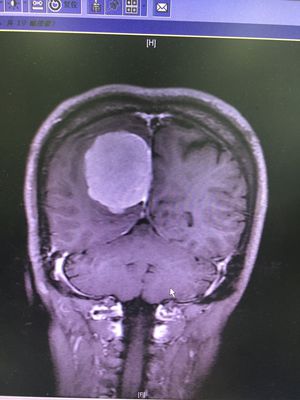

Meningioma

One of the commonest brain tumor these days . Affects meninges and it has good prognostic fate . Patients present with symptoms of increased icp .